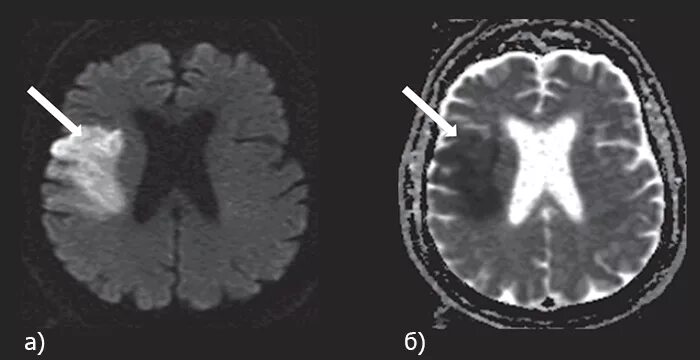

Очаг ограничения диффузии